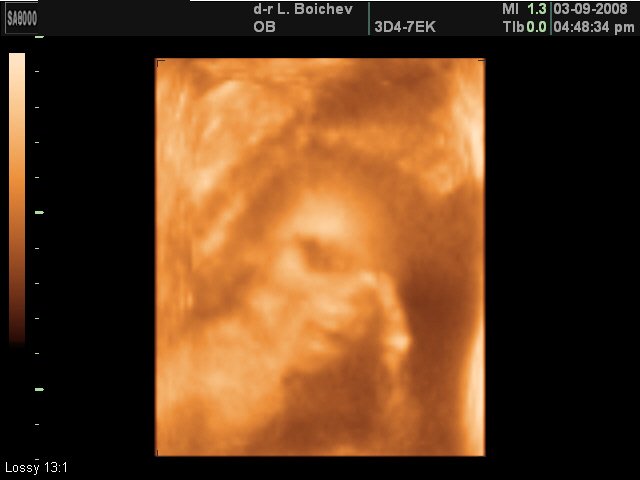

преди

и сега

- има и по-ранни, но не съм ги качила в интернет. Тази е на няколко дни в къщи.